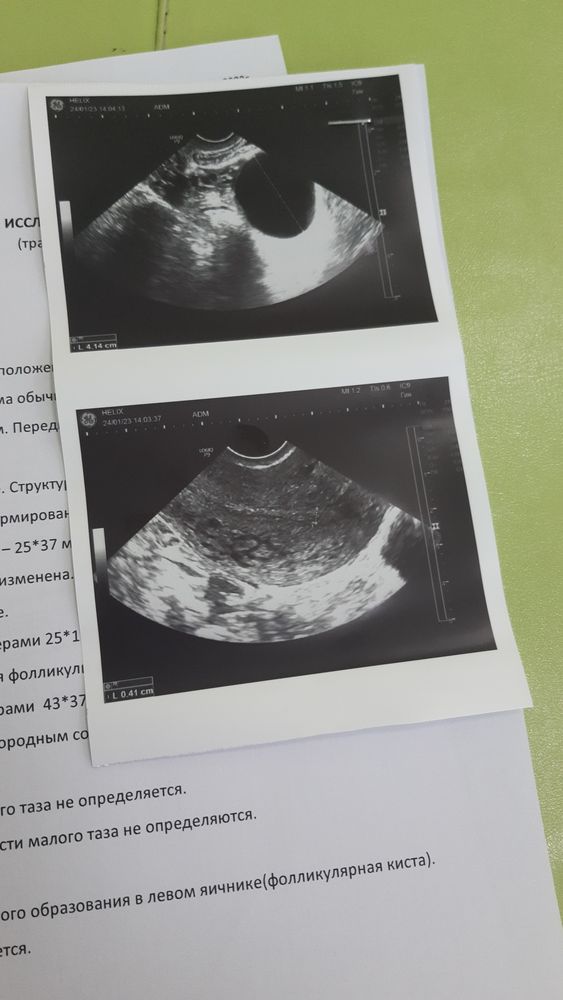

Девочки может кто сталкивался с таким. 21.01 началась задержка, но до этого три дня тесты были положительные, и дней 10 очень болели груди, 23.01 пошли м , на следующий день пошла на узи и сдала хгч. Фото приложу. Узист сказала что даже овуляции не было но тесты делала разных фирм, даже 24 при месячных тест был положительным только уже полоска была слабая . К геникологу на следующей неделе.